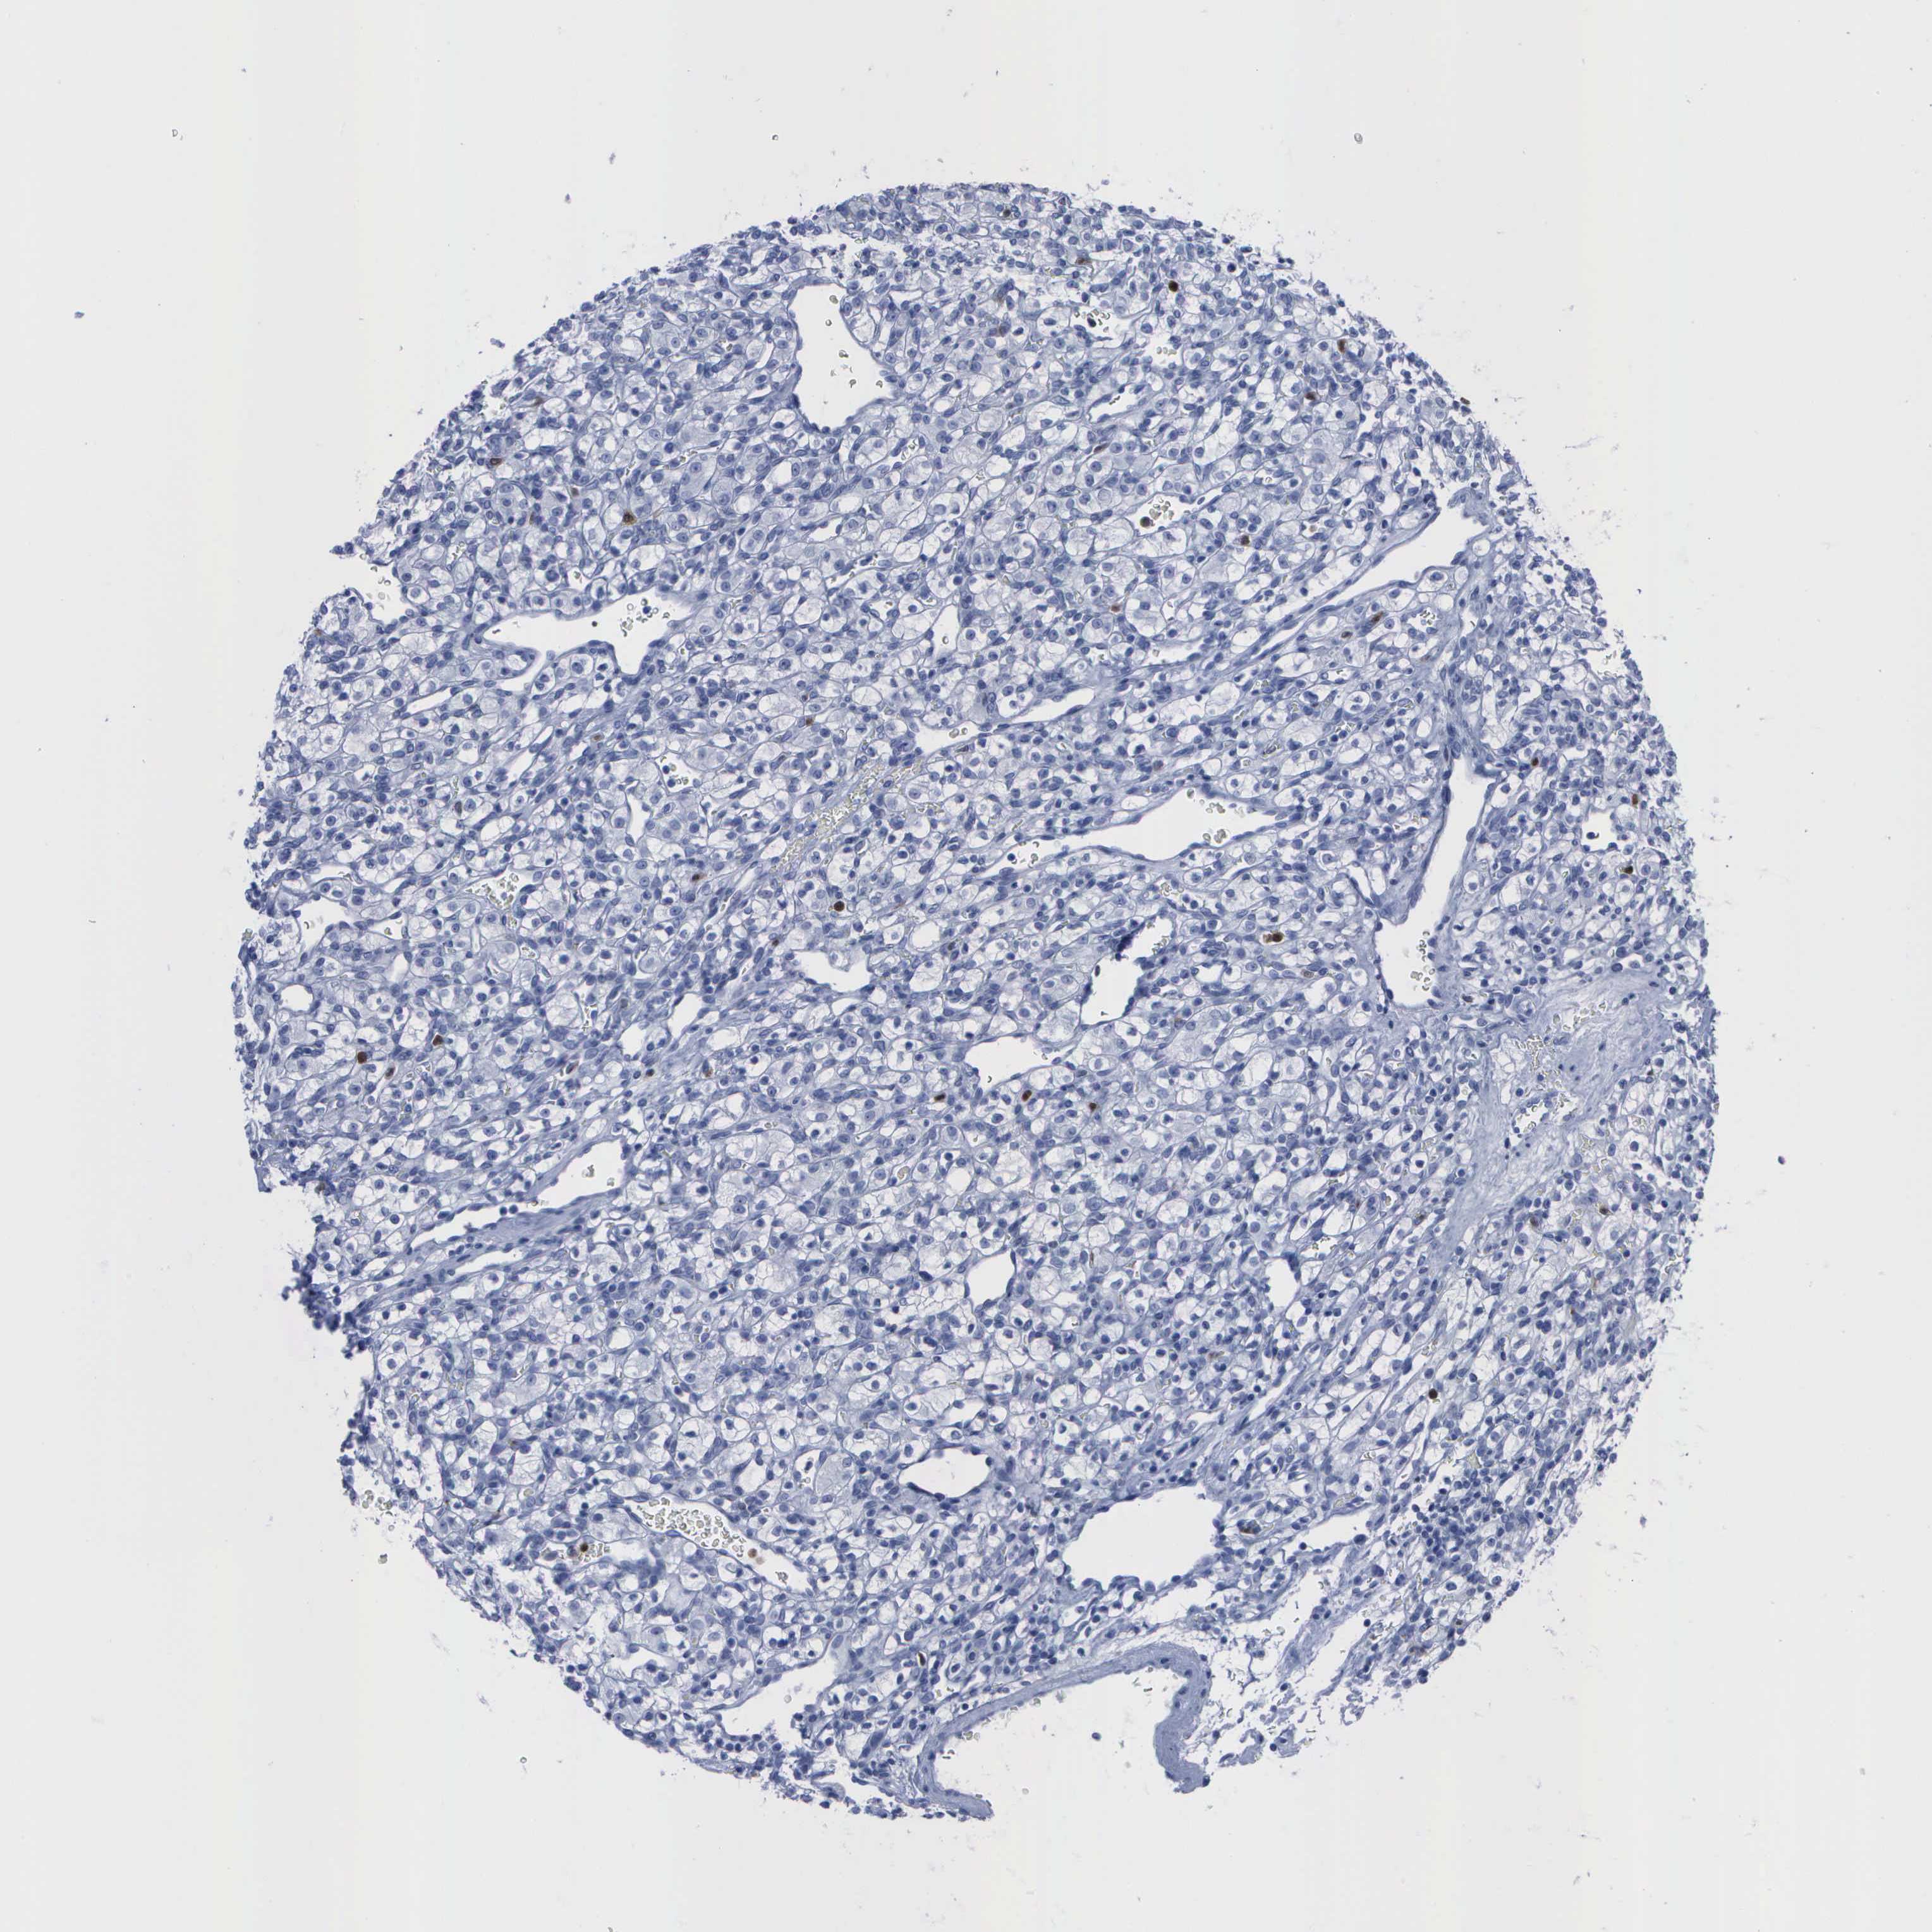

KIDNEY RENAL CLEAR CELL CARCINOMA (VALIDATION) - Interactive survival scatter ploti

The Survival Scatter plot shows the clinical status (i.e. dead or alive) for all individuals in the patient cohort, based on the same data that underlies the corresponding Kaplan-Meier plots. Patients that are alive at last time for follow-up are shown in blue and patients who have died during the study are shown in red.

The x-axis shows the expression levels (FPKM) of the investigated gene in the tumor tissue at the time of diagnosis. The y-axis shows the follow-up time after diagnosis (years). Both axes are complimented with kernel density curves demonstrating the data density over the axes. The top density plot shows the expression levels (FPKM) distribution among dead (red) and alive patients (blue). The right density plot shows the data density of the survived years of dead patients with high and low expression levels respectively, stratified using the cutoff indicated by the vertical dashed line through the Survival Scatter plot. This cutoff is automatically defined based on the FPKM cutoff that minimizes the p-score. The cutoff can be changed by dragging the vertical line or by entering a cutoff value in the square labeled "Current cut-off".

Under the Survival Scatter plot the p-score landscape (black curve; left axis) is shown together with dead median separation (red curve; right axis). Dead median separation is the difference in median mRNA expression between patients who have died with high and low expression, respectively. It is calculated as follows: median FPKM expression of dead patients with high expression - median FPKM expression of dead patients with low expression. This is intended to aid the user in visually exploring custom cutoffs and the associated p-scores and dead median separation.

Individual patient data is displayed and can be filtered by clicking on one or more of the category buttons on the top of the page. Categories describing expression level and patient information include: high, low, alive, dead, female, male and tumor stages. The scale of the x-axis can be toggled between linear and log-scale by clicking on the "x log" button. Mouse-over function shows TCGA ID, patient information and mRNA expression (FPKM) for each patient.

& Survival analysisi

Kaplan-Meier plots summarize results from analysis of correlation between mRNA expression level and patient survival. Patients were divided based on level of expression into one of the two groups "low" (under cut off) or "high" (over cut off). X-axis shows time for survival (years) and y-axis shows the probability of survival, where 1.0 corresponds to 100 percent.

CSTA is not prognostic in Kidney Renal Clear Cell Carcinoma (validation)

Best expression cut offi

Based on the FPKM value of each gene, patients were classified into two groups and association between prognosis (survival) and gene expression (FPKM) was examined. The best expression cut-off refers the FPKM value that yields maximal difference with regard to survival between the two groups at the lowest log-rank P-value. Best expression cut-off was selected based on survival analysis .

When clicking on this number, the vertical dashed line indicating cut-off, the interactive survival plot, and the Kaplan-Meier curve will be adjusted to show results based on the best expression cut-off.

: 19.04

P scorei

Log-rank P value for Kaplan-Meier plot showing results from analysis of correlation between mRNA expression level and patient survival.

N/A

TCGA RNA samplesi

RNA-seq data is reported as average FPKM (number Fragments Per Kilobase of exon per Million reads), generated by the The Cancer Genome Atlas (TCGA) .

Normal distribution across the dataset is visualized with box plots, shown as median and 25th and 75th percentiles. Points are displayed as outliers if they are above or below 1.5 times the interquartile range. FPKM values of the individual samples are presented next to the box plot.

Average pTPM 15.1

Number of samples 100